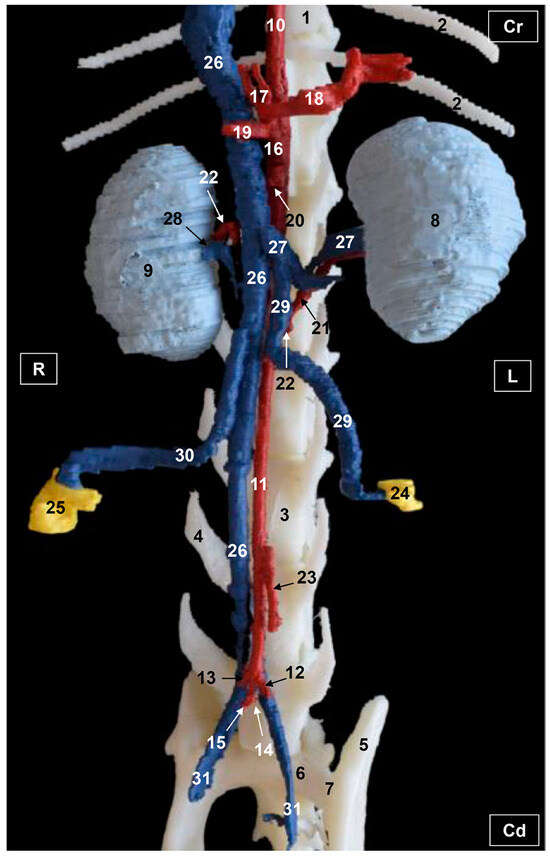

3.2. Computed Tomography Angiography and 3D Printing

3.2.1. Arterial System

3.2.2. Venous System